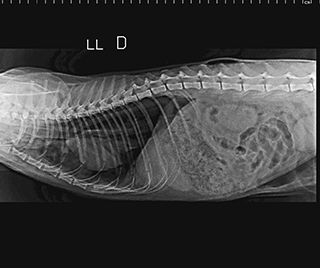

Radiologia Digital Direta / Digital Radiography

As radiografias geradas digitalmente podem ser transmitidas para iPad Apple®, notebooks e smartphones.

iPad com tela Retina Apple® possibilita a visualização das imagens com maior qualidade diagnóstica.

O treinamento aborda a geração das radiografias, a edição digital das imagens, e também a

escolha adequada de técnicas radiográficas como kilovoltagem, corrente elétrica e tempo de exposição.